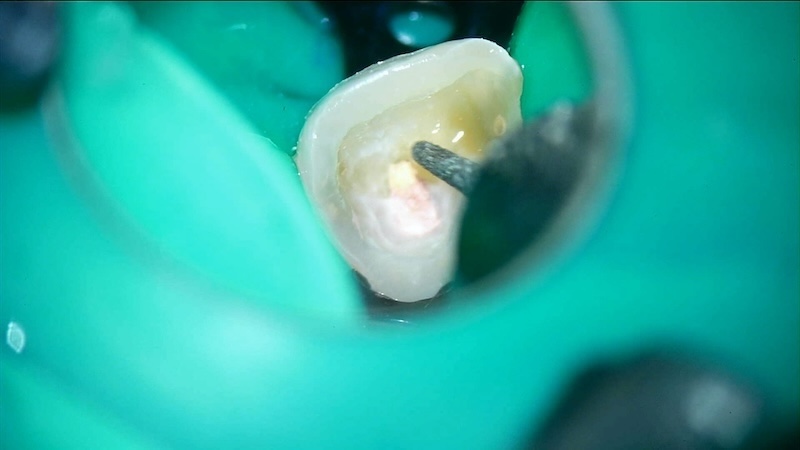

■ ラバーダムによる無菌環境

無菌環境を作るためのラバーダム

唾液や細菌の侵入を完全に遮断し、再感染を防ぎます。

■ 徹底した感染除去

感染源を徹底的に除去

古いガッタパーチャを除去し、感染した組織を丁寧に洗浄・消毒します。

実際、この症例でも強い感染が確認されました。